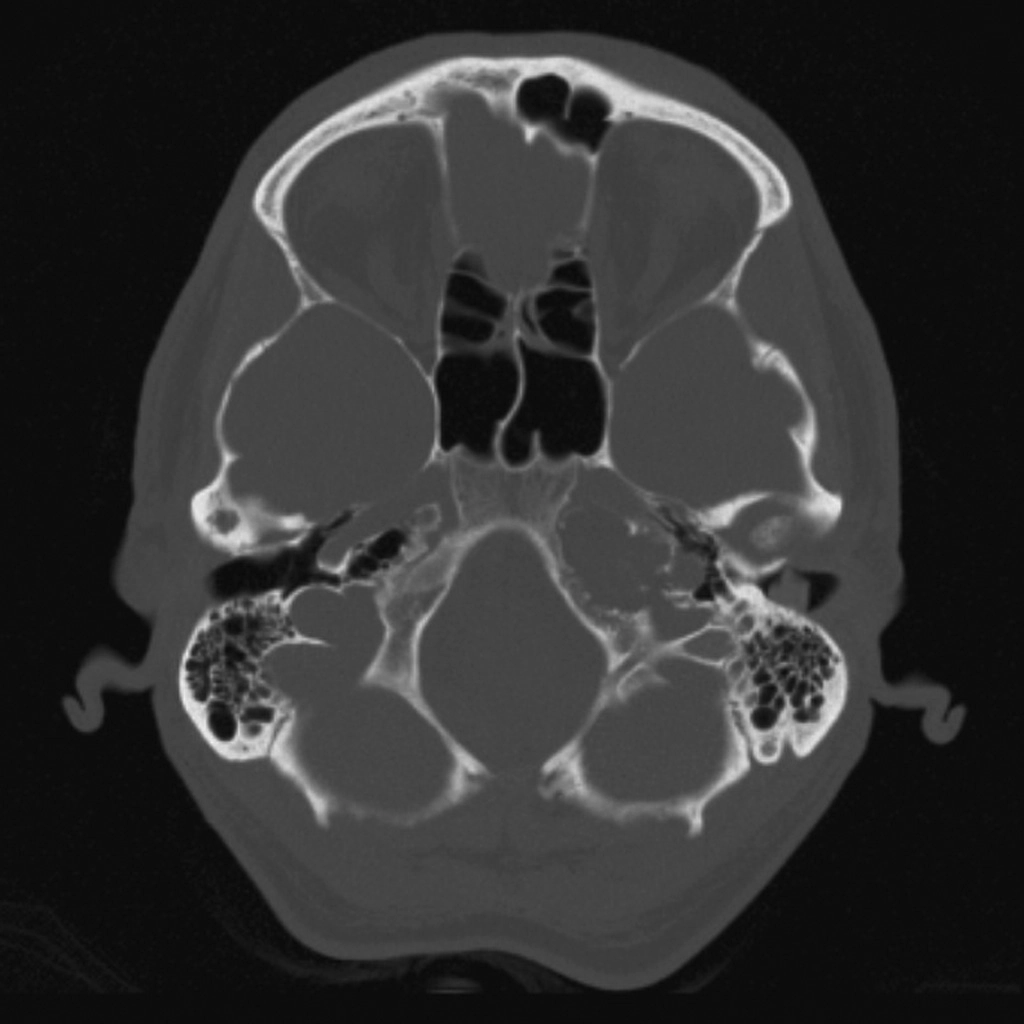

Viêm đỉnh xương đá (Petrous apicitis)